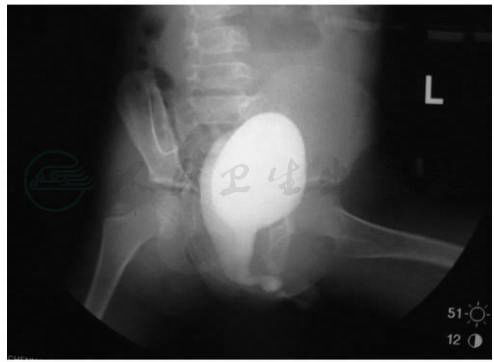

尿道下裂(hypospadias)是很常见的男性外生殖器畸形,由于前尿道发育不全,胚胎发育过程中尿生殖沟没有能自后向前在中线完全闭合,造成尿道口达不到正常位置的阴茎畸形。尿道开口可出现在正常舟状窝至近侧会阴部途径上,部分病例可伴发阴茎下弯。主要表现为尿道外口异位,阴茎背侧包皮堆积,阴茎弯曲,严重者不能站立排尿(图1)。

图1尿道下裂